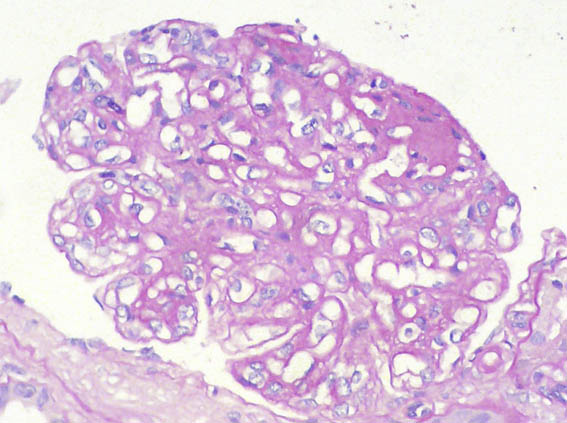

Figure 2.

H&E, X400.